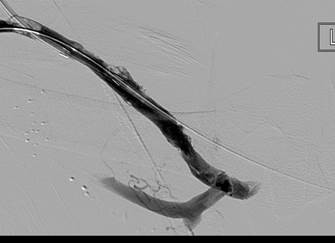

Imagen tras la activación del sistema AngioJet en el lado arterial del injerto AV.